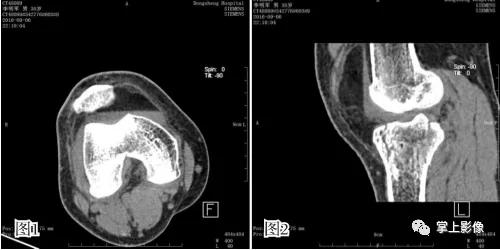

图1 、2为同一患者胫骨平台骨折合并积脂血症不同界面的 CT 表现,液平上方为脂肪,下方为关节内出血,可见单液-液平面征。图 3 为髌上囊积脂血征,胫骨平台骨折合并腓骨小头骨折。图 4 为 1 例隐匿性骨折患者,男,48 岁,车祸外伤,左膝关节活动受限,普通 X 线检查提示髌上囊内密度升高,常规平扫见脂液平面,经薄层重建充分显示左髌骨外侧缘撕脱骨折

- 关节内骨折之后从撕裂处骨膜组织或者是骨髓腔内溢出的血液与脂肪同时进入到关节内囊中,同时因关节软骨及滑膜释放的一种酶能发挥阻止血凝块形成的作用,导致进入关节囊内的血液无法凝结,并与脂肪分离,密度小的脂肪浮于上层,而密度大的血液沉于下层,构成脂-血平面。这也是创伤性关节积脂血症患者在接受影像学诊断中最重要也最具特征性的表现,也是单液-液平面形成的原因